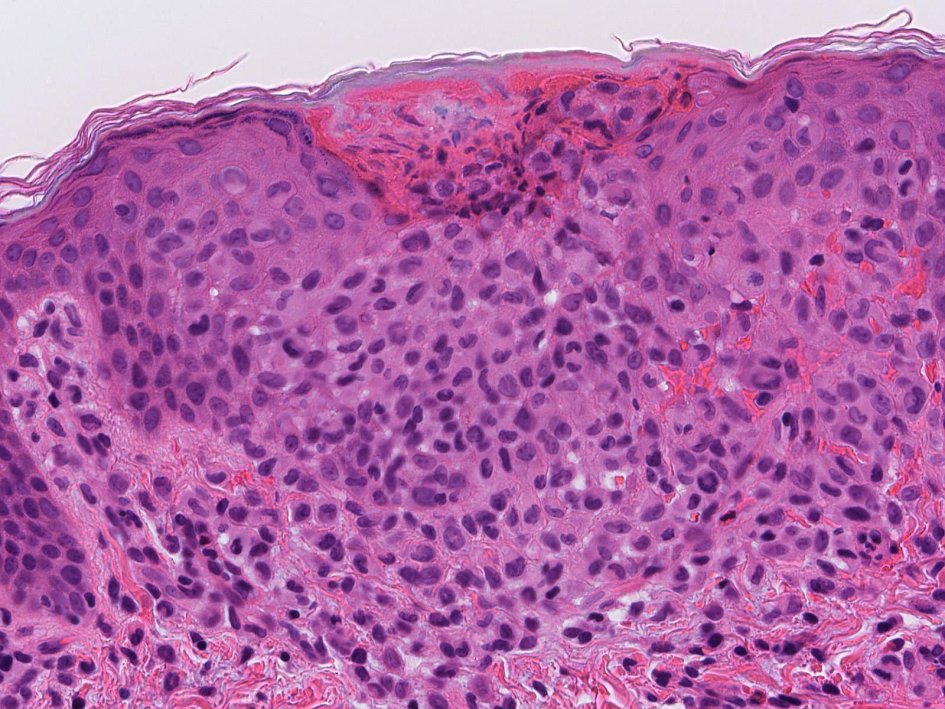

0歳女児 皮膚に1mm大の丘疹が多発, びらんを伴っている.肝脾腫あり

皮膚組織所見

丘疹のルーペ像HE X10HE X40

病理組織診断:Langerhans cell histiocytosis, multifocal multisysem disease